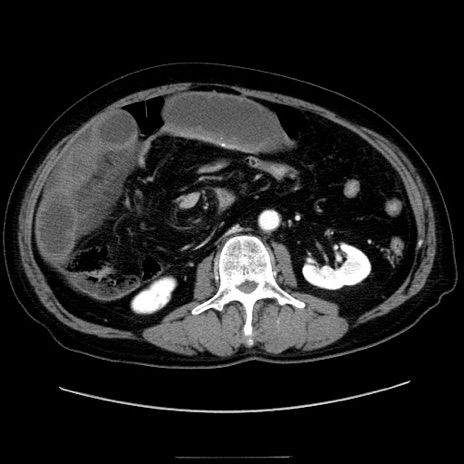

症例30(横断像)

【症例】80歳代男性

【現病歴】約6時間前から臍下部痛が出現。次第に腹部膨隆・背部痛も生じてきたため来院。背部痛の場所は変化しない。

【身体所見】意識清明、BT 36.3℃、BP  131/87mmHg、P 87bpm、SpO2 100%(RA)、臍周囲自発痛・圧痛あり、反跳痛なし、自発痛部位に一致して板状硬あり、腹部膨隆、腸雑音減弱、CVA tenderness両側陰性。

【データ】WBC 19600、CRP 0.33